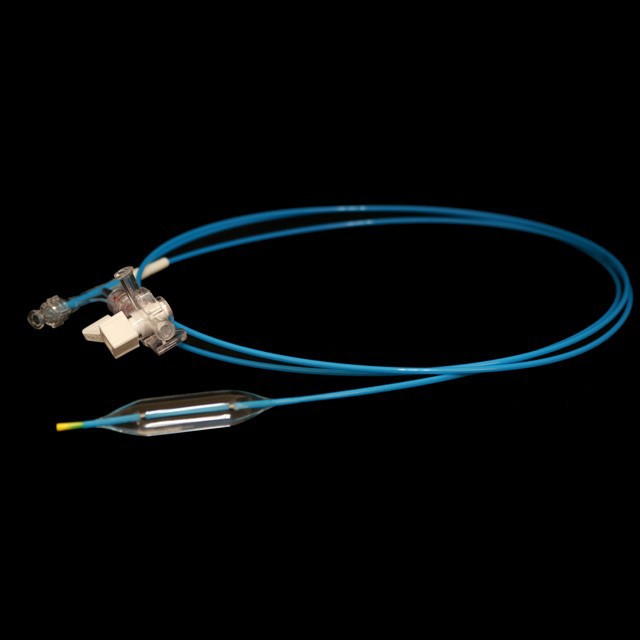

●Tað er hóskandi til vaksin og ungdóm í dilatatiónsvirkseminum av meltingarvegstriktinum undir endoskopum.

●Pre-input 0.035"leiðaratráður við mjúkum oddi og merki,sum er lættari at meta um longdina á innaru duty-tráðinum.